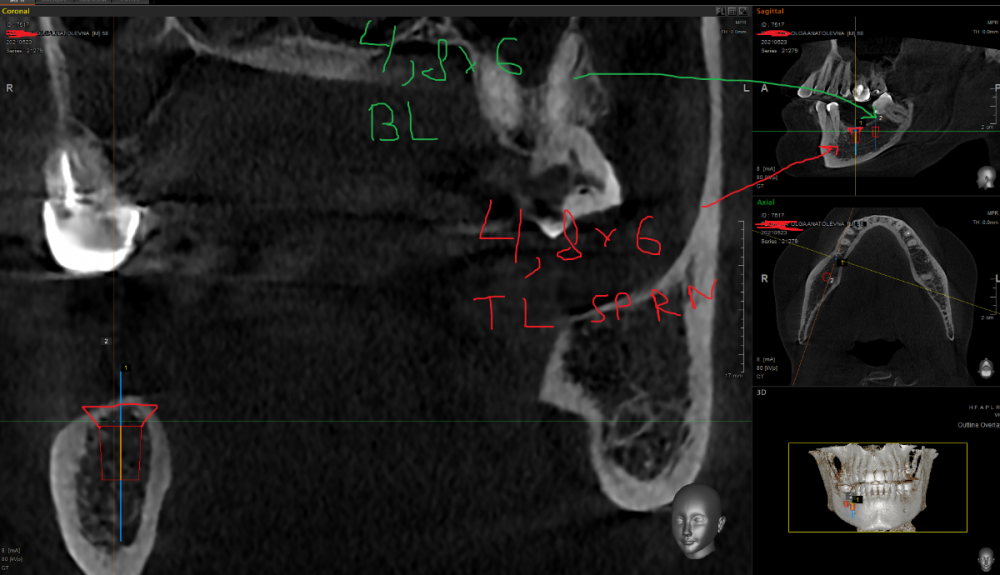

It'sGeorgy Опубликовано 17 сентября, 2021 Поделиться Опубликовано 17 сентября, 2021 (изменено) Добрый день! У пациентки тонкий биотип. Десна над планируемым 4.6 имплантатом была не более, чем в 1мм в высоту. Первым этапом уже удалил 4.8, положил с бугра небольшой сст(большой брать неоткуда) в область 4.6 и ушил. Надеюсь, получу хотя бы 1.5мм на этапе имплантации. С кератинизацией больших проблем нет. Планирую короткие(6мм) имплантаты, ибо если ставить 4.6 длинной 8мм возникает вот такая инт близость с каналом. На такой риск идти не готов: Скрытый текст Идем дальше: 4.6, наверняка, придется немного затопить, ибо много десны я получить своим трансплантатом вряд ли смогу, а заглублением - смогу. И вот тут начинаются проблемы: плоскости 4.6 и 4.7 очень отличаются по высоте. Выходом вижу ставить 4.6 TL, а 4.7 BL: Скрытый текст Протезирование на совести ортопеда. Мое мнение: надо будет шинировать. 1.6, скорее всего, на удаление пойдет с последующим синусом и винтом. Альтернативный план: покупать мукодерм, повторно подкладывать снова в область 4.6, пытаться растить десну и ставить в позиции 4.6 импл BL 4,8x8 вообще без заглубления. Правильно ли мыслю? Есть какие-то советы? Изменено 17 сентября, 2021 пользователем It'sGeorgy Ссылка на комментарий